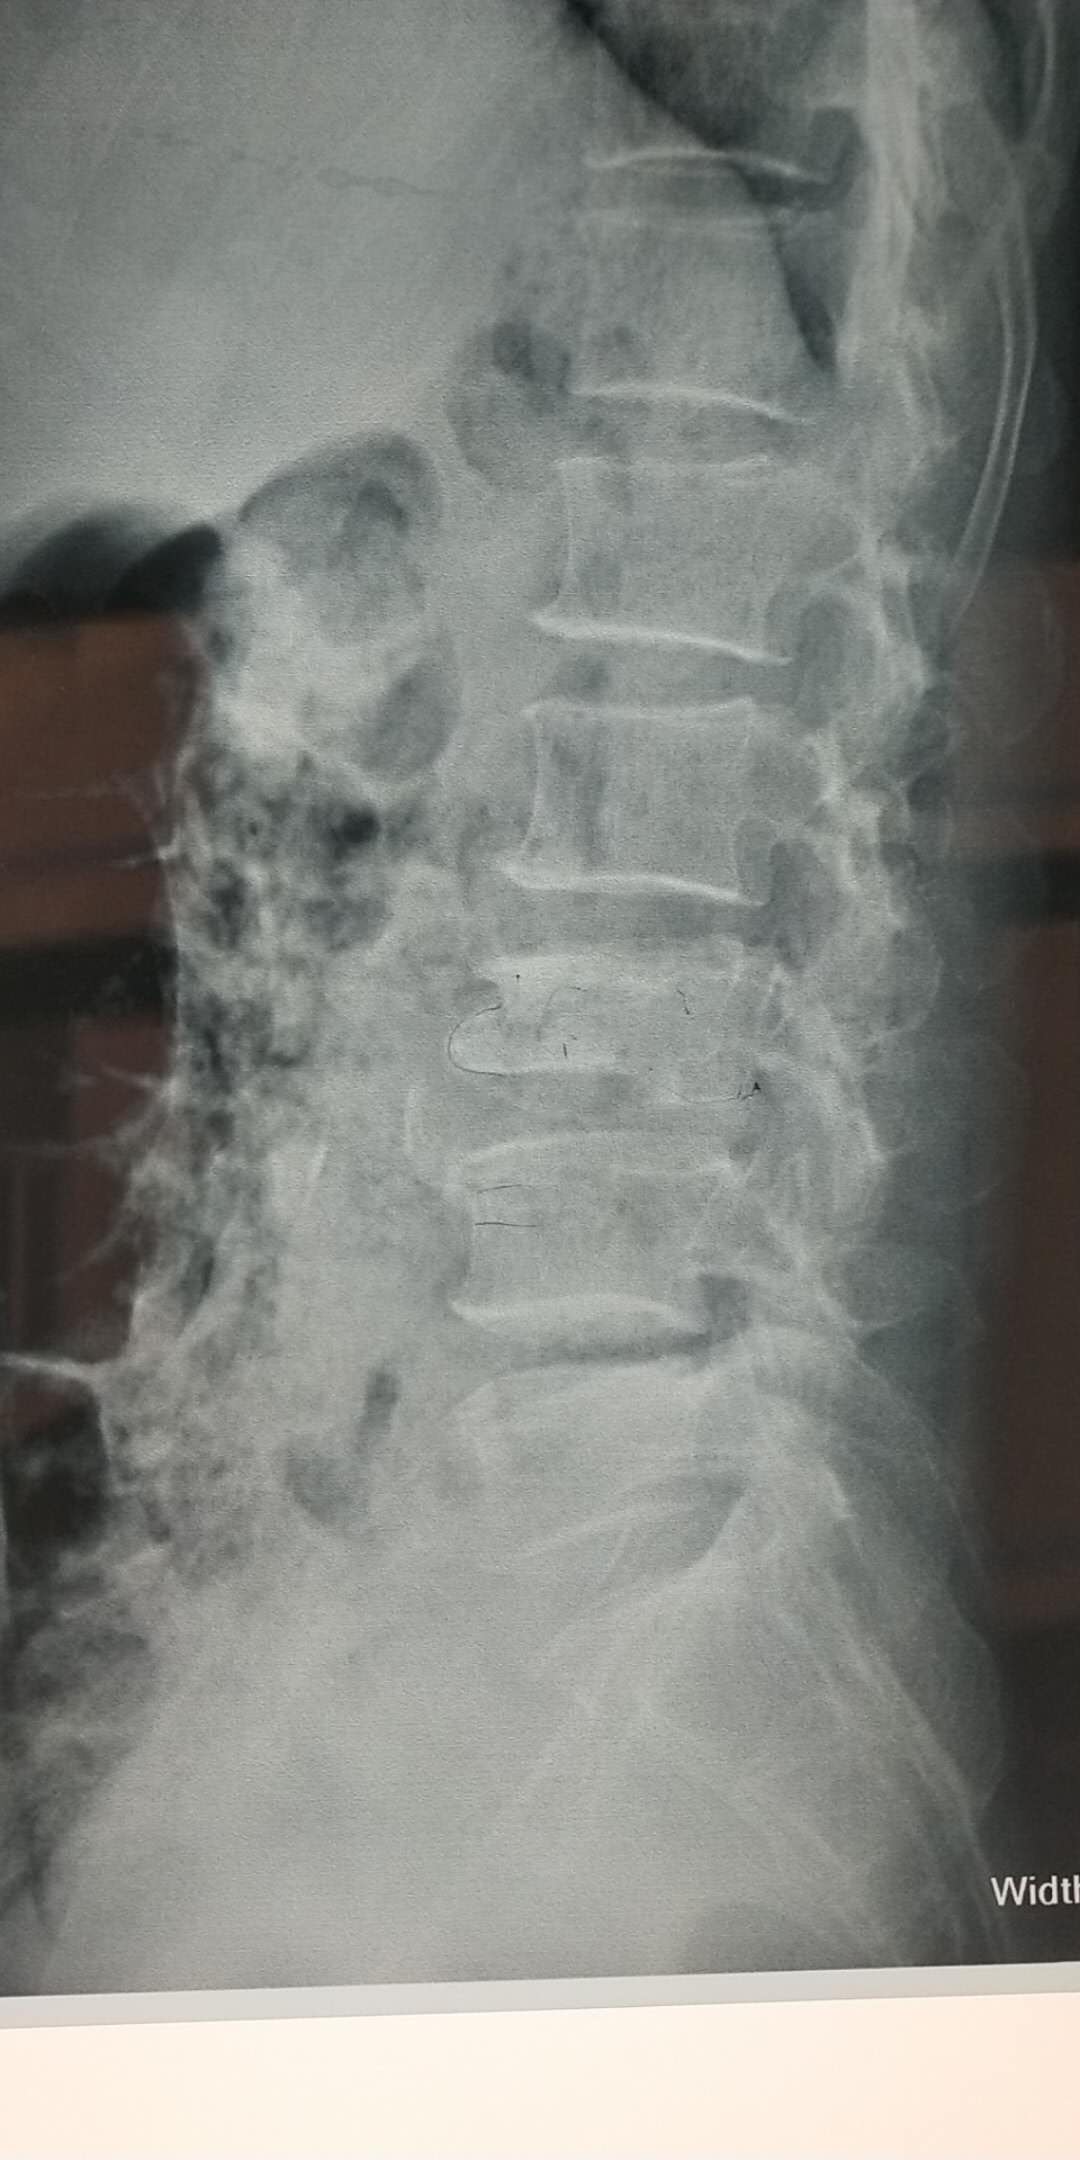

術(shù)后片子

骨一科已成功為數十名患者成功開(kāi)展PVP手術(shù)。僅今年3月份,在何光亮主任的帶領(lǐng)下,骨一科已經(jīng)成功開(kāi)展5例PVP手術(shù),術(shù)后患者相當滿(mǎn)意,全部患者術(shù)后可自行行走,擺脫臥床。3月21日患者王某,90歲,因摔傷致腰部疼痛3天為主訴入院,診斷腰1椎體骨折、骨質(zhì)疏松癥、高血壓等,住院后經(jīng)過(guò)科室術(shù)前討論,何主任為患者制定了PVP手術(shù)方案,于3月22日在行腰1椎體壓縮性骨折經(jīng)皮穿刺椎體成形骨水泥填充術(shù),術(shù)后24小時(shí)患者即下床活動(dòng),術(shù)后一周患者痊愈出院,隨訪(fǎng)患者已基本恢復到術(shù)前狀態(tài)。